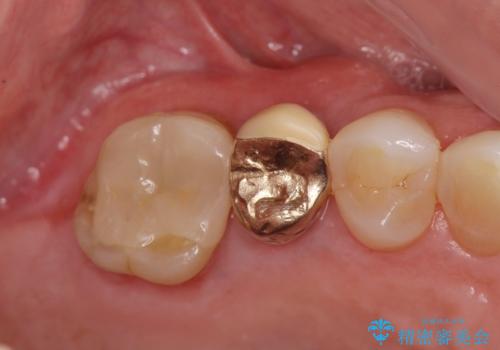

抜去後の機能回復方法としてインプラント、入れ歯以外の方法を希望されたためブリッジでの咬合機能回復を行っていくこととなりました。